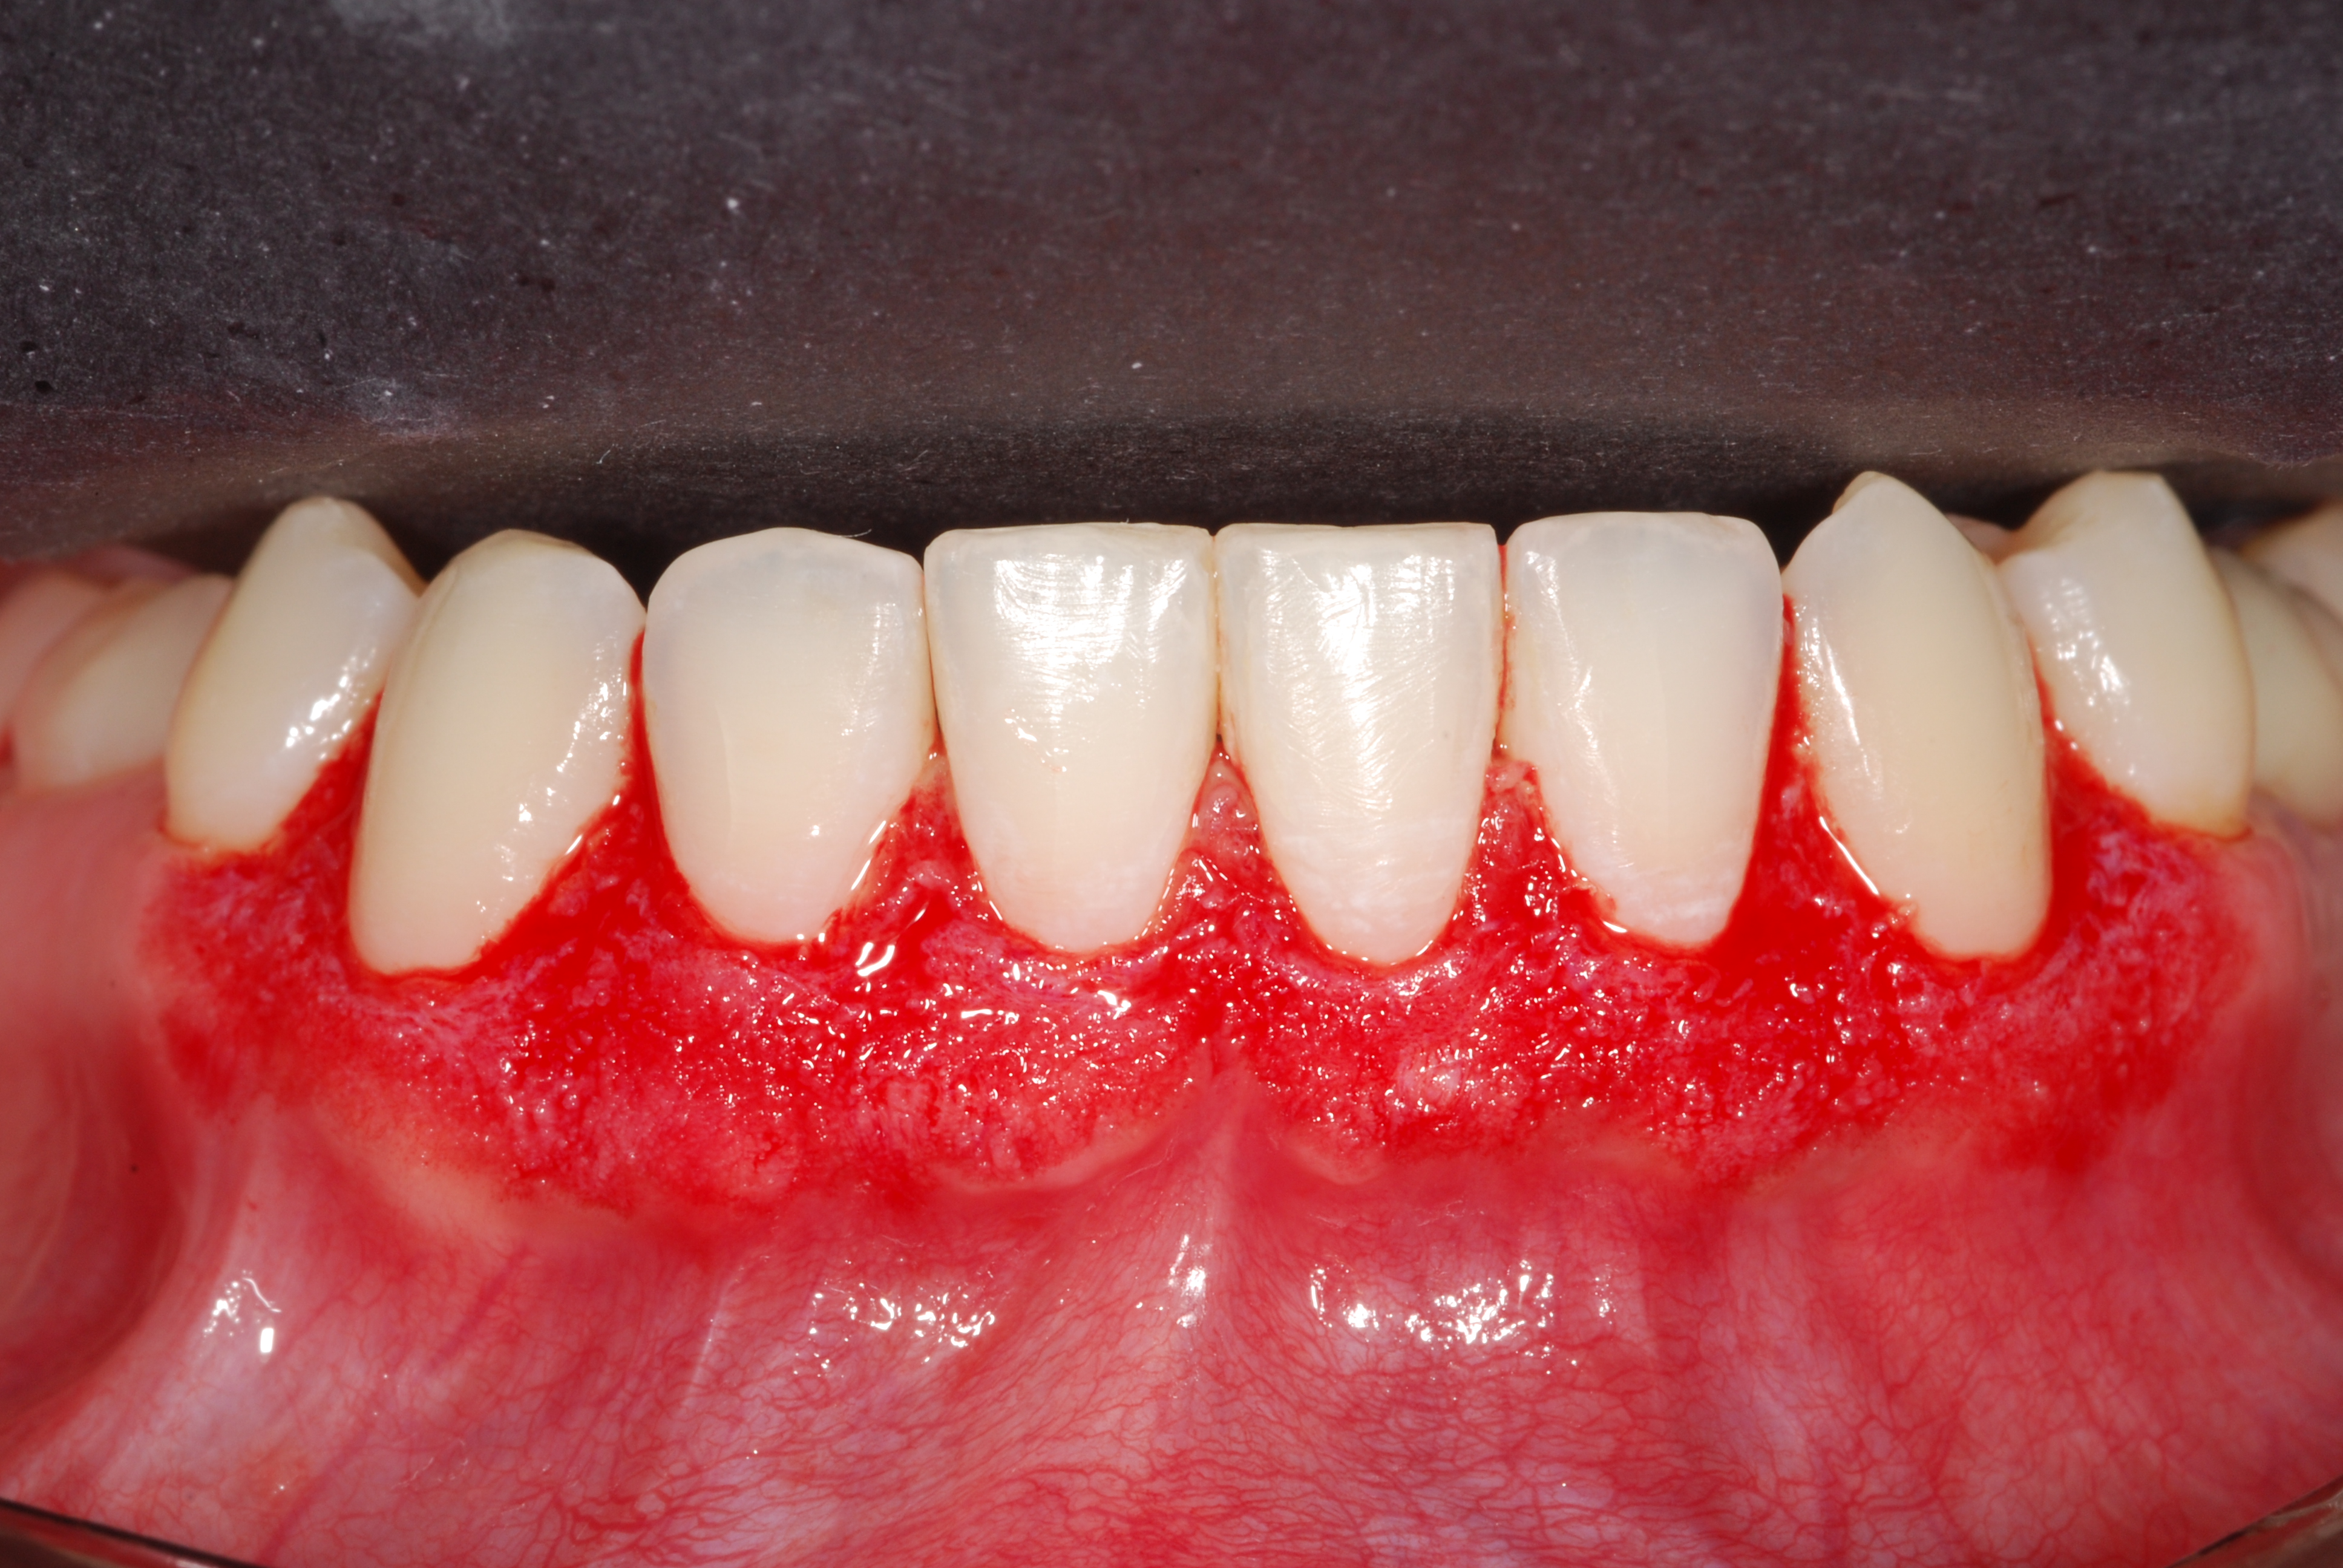

The presence of diastema, between anterior teeth, distorts a pleasing smile by concentrating the observer’s attention on the spaces. The patient’s needs and expectations must be considered in the process of treatment planning to ensure satisfaction with the treatment outcomes. There are many forms of therapy that can be used for diastema closure. A carefully developed diagnosis, which includes a determination of the causal elements and advanced treatment planning, allows the most appropriate treatment to be selected for each case. The aim of this paper is present a multidisciplinary approach as a solution to multiple diastemas in the anterior region using gingival tissue recontouring and direct adhesive restorations, with minimum wear of the dental structure, after the orthodontic intervention discussing the minimal intervention to obtain imperceptive and aesthetic final restoration. Thirty-six months after the treatment was carried out, the final aesthetic was maintained with all dental element details and gingival tissue harmony, without recurrence of periodontal pockets and the preservation of the tooth color and shape.